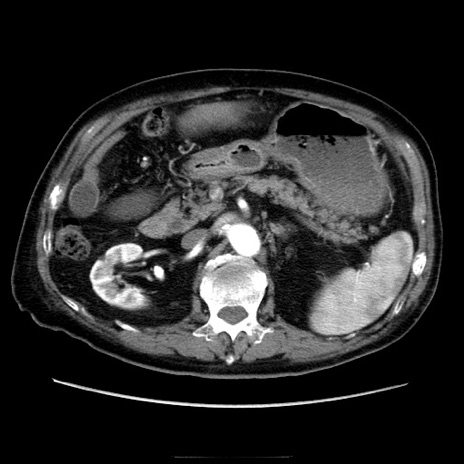

症例21(横断像)

【症例】70歳代男性

【主訴】腹痛

【現病歴】肝硬変・肝細胞癌にてかかりつけの方。約9時間前に食後より腹痛出現。症状が徐々に増悪し、嘔吐出現したため来院。

【既往歴】肝硬変、肝細胞癌(RFA、TACE後)

【身体所見】意識清明、表情苦悶様、BT 36℃、BP 129/78mmHg、P 88bpm、SpO2 97%(RA)、右上腹部から心窩部にかけて圧痛あり、反跳痛なし、筋性防御あり。

【データ】WBC 5800、CRP 0.16